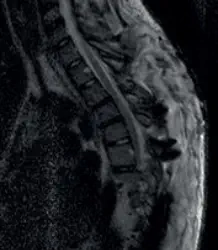

Jazz Band-System Innovative Lösung zur posterioren Fixierung der Wirbelsäule Das Jazz™ Band-System von IMPLANET bietet eine moderne und flexible Methode zur dorsalen Stabilisierung der Wirbelsäule. Es kombiniert ein biokompatibles Polyesterband, einen Titan-Connector und ein integriertes Verriegelungselement, um eine zuverlässige temporäre Stabilisierung zu gewährleisten – bis zur vollständigen Knochenfusion. Das System ist vielseitig einsetzbar und kann sowohl eigenständig als auch in Kombination mit anderen Implantaten wie Pedikelschrauben oder Haken verwendet werden. Es bietet maximale Flexibilität in der chirurgischen Anwendung und ist besonders geeignet für die Behandlung von degenerativen Erkrankungen, Deformitäten und traumatischen Läsionen der Wirbelsäule. Vorteile des Jazz™ Band-Systems: Echte dreidimensionale Korrektur: Dank seines einfachen und leistungsstarken Band-Spanners gewährleistet Jazz™ Evo eine postero-mediale Translation und Derotation, insbesondere durch einen Wirbelsäulendetorsionseffekt usw. Zuverlässige Anwendung – unabhängig von der Knochenqualität: Dank seiner breiten Auflagefläche verteilt das Jazz™ Band die erzeugte Spannung über eine große Oberfläche, wodurch eine hohe Stabilität erzeugt wird, unabhängig von der Knochenqualität. Reduzierte Strahlenbelastung: Durch die geringere Anzahl von Pedikelschrauben implantierungen reduziert die Jazz™ Technologie die intraoperative Röntgenstrahlenbelastung des Patienten und des Operationsteams. Bessere Ergebnisse durch kürzere Operationsdauer: Geringerer Blutverlust Erhaltung von Knochensubstanz Weniger Komorbiditäten Maximale Optionen für eventuelle zukünftige Fixierungsoptionen Optimierte postoperative Überwachung: Da sich kein Fremdmaterial (Metall) im Pedikel und im Wirbelkanal befindet, eliminiert Jazz™ Evo Probleme mit Verschattungen und Artefakten. Es ermöglicht optimale postoperative Untersuchungen der neurologischen Strukturen, u.a. mit Hilfe von MRT. Steril verpackte Implantate: Für höchste Sicherheit und sofortige Einsatzbereitschaft im OP.​

Jazz™ Band-System Innovative Lösung zur posterioren Fixierung der Wirbelsäule Das Jazz™ Band-System von IMPLANET bietet eine moderne und flexible Methode zur dorsalen Stabilisierung der Wirbelsäule. Es kombiniert ein biokompatibles Polyesterband, einen Titan- Connector und ein integriertes Verriegelungselement, um eine zuverlässige temporäre Stabilisierung zu gewährleisten – bis zur vollständigen Knochenfusion.​ Das System ist vielseitig einsetzbar und kann sowohl eigenständig als auch in Kombination mit anderen Implantaten wie Pedikelschrauben oder Haken verwendet werden. Es bietet maximale Flexibilität in der chirurgischen Anwendung und ist besonders geeignet für die Behandlung von degenerativen Erkrankungen, Deformitäten und traumatischen Läsionen der Wirbelsäule. Vorteile des Jazz™ Band-Systems: Echte dreidimensionale Korrektur: • Dank seines einfachen und leistungsstarken Band-Spanners gewährleistet Jazz™ Evo eine postero-mediale Translation und Derotation, insbesondere durch einen Wirbelsäulendetorsions- effekt usw. Zuverlässige Anwendung – unabhängig von der Knochenqualität: • Dank seiner breiten Auflagefläche verteilt das Jazz™ Band die erzeugte Spannung über eine große Oberfläche, wodurch eine hohe Stabilität erzeugt wird, unabhängig von der Knochen- qualität. Reduzierte Strahlenbelastung: • Durch die geringere Anzahl von Pedikelschrauben implantierungen reduziert die Jazz™ Technologie die intraoperative Röntgenstrahlenbelastung des Patienten und des Operationsteams. Bessere Ergebnisse durch kürzere Operationsdauer: • Geringerer Blutverlust • Erhaltung von Knochensubstanz • Weniger Komorbiditäten • Maximale Optionen für eventuelle zukünftige Fixierungsoptionen Optimierte postoperative Überwachung: Da sich kein Fremdmaterial (Metall) im Pedikel und im Wirbelkanal befindet, eliminiert Jazz™ Evo Probleme mit Verschattungen und Artefakten. Es ermöglicht optimale postoperative Untersuchungen der neurologischen Strukturen, u.a. mit Hilfe von MRT. Steril verpackte Implantate: • Für höchste Sicherheit und sofortige Einsatzbereitschaft im OP.